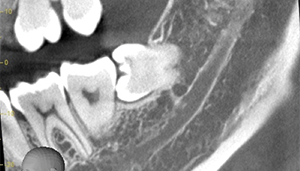

- 抜歯前写真(レントゲン)

- 抜歯前写真(CT画像)

| 主訴 | 左下親知らずがたまに痛み、できれば痛くなく抜きたい |

| 親知らずの生え方 | 完全に埋まっている、横向きに生えている |

| 抜歯時間 | 50分 |

| 費用 | 約8,000円(保険診療、CT代含む) |

| 抜歯内容 | 左下親知らずが横向きになって半分埋まっている状態だったため、麻酔を行い、親知らずの奥の歯ぐきに切開をいれ、歯が囲んでいる骨を削り、歯の頭の部分を削って出し、その後根の部分に器具をかけて抜歯しました。 親知らずが一部神経に近い部分があったため、術後に麻痺が出る可能性がありました。このケースでは事前にCTを撮影し、歯の位置、根の方向、神経との距離を確認していたため、幸い麻痺が出ることはありませんでした。 術後1週間経過して糸取りをして治療は終了となりました。抜歯後3日間は腫れと痛みで大変だったが、糸取りをする頃には痛みも腫れも無くなったと患者さまも喜んでおられました。 |